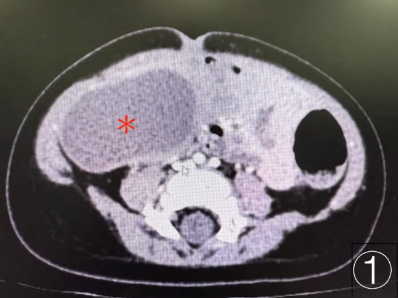

1.5厘米小孔的精准手术,首儿所胸部及肿瘤外科为8岁女孩卸下胰腺重担

8岁,本应是奔跑嬉闹、无忧无虑的年纪。可对于女孩小沐(化名)来说,过去一年多的时光,却被胰腺病灶蒙上阴霾,一家人四处辗转求医,只为给孩子寻求最稳妥的治疗方案。 一次意外外伤后的检查,开启了小沐的求医之路。在北京一家医院,小沐接受了腹部超声检查,查出胰腺体尾部有约2厘米占位性包块。胰腺位于腹腔深部...